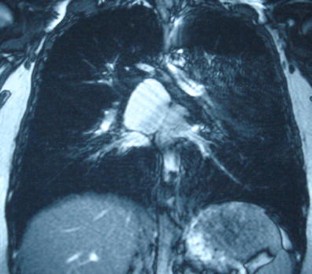

Fig. 3